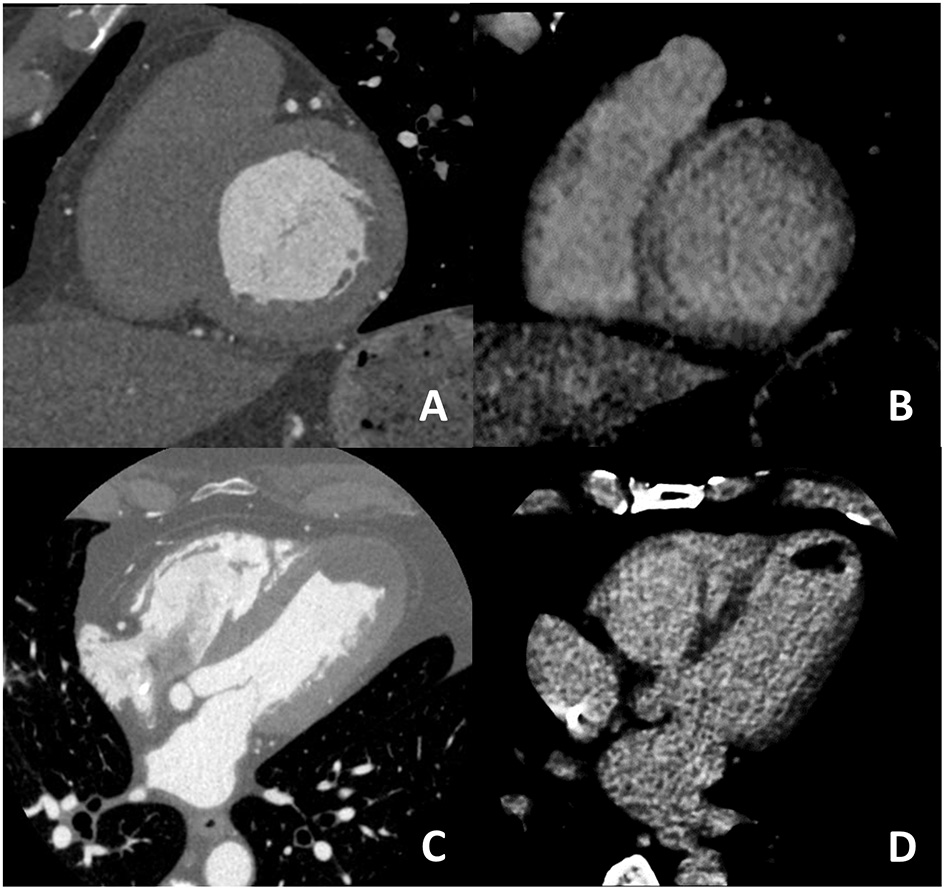

For what concern non-ischemic fibrosis, a validation study was performed in 2014 including 24 patients with hypertrophic phenotype who underwent both CCT and CMR for myocardial fibrosis evaluation (Figure 6). On a per-patient basis, CCT had a 100% sensitivity for myocardial fibrosis vs. CMR and mean myocardial scar area resulted of 2.2 ± 1.4 cm2 in CCT vs. 2.9 ± 2.4 cm2 in CMR; of interest, authors reported that the relative intensity ratio between normal remote myocardium and area of myocardial fibrosis in CT was 1.8 ± 0.3 (48). Similar promising results have been recently reported in a consecutive cohort of patients with sarcoidosis evaluated with both CCT and CMR (49). For optimal evaluation of myocardial fibrosis at late CT scan, dedicated post-processing analysis is needed, as previously described (50). More precisely, an 8–10 mm thickness in short-axis LV view should be obtained and narrow window and level settings (W300, L150) are suggested (Figure 5).

Figure 6

In (A,B) an example of non-ischemic fibrosis on the interventricular septum is shown; more specifically, in (A) angiographic phase CT is presented with corresponding late CT acquisition well demonstrating non-ischemic mid-wall myocardial fibrosis in (B). In (C,D) a case of ischemic cardiomyopathy is presented; an apical left ventricular thrombus is evident both at first pass CT (C) and at late phase CT (D) from which the ischemic subendocardial fibrosis could be evidenced.